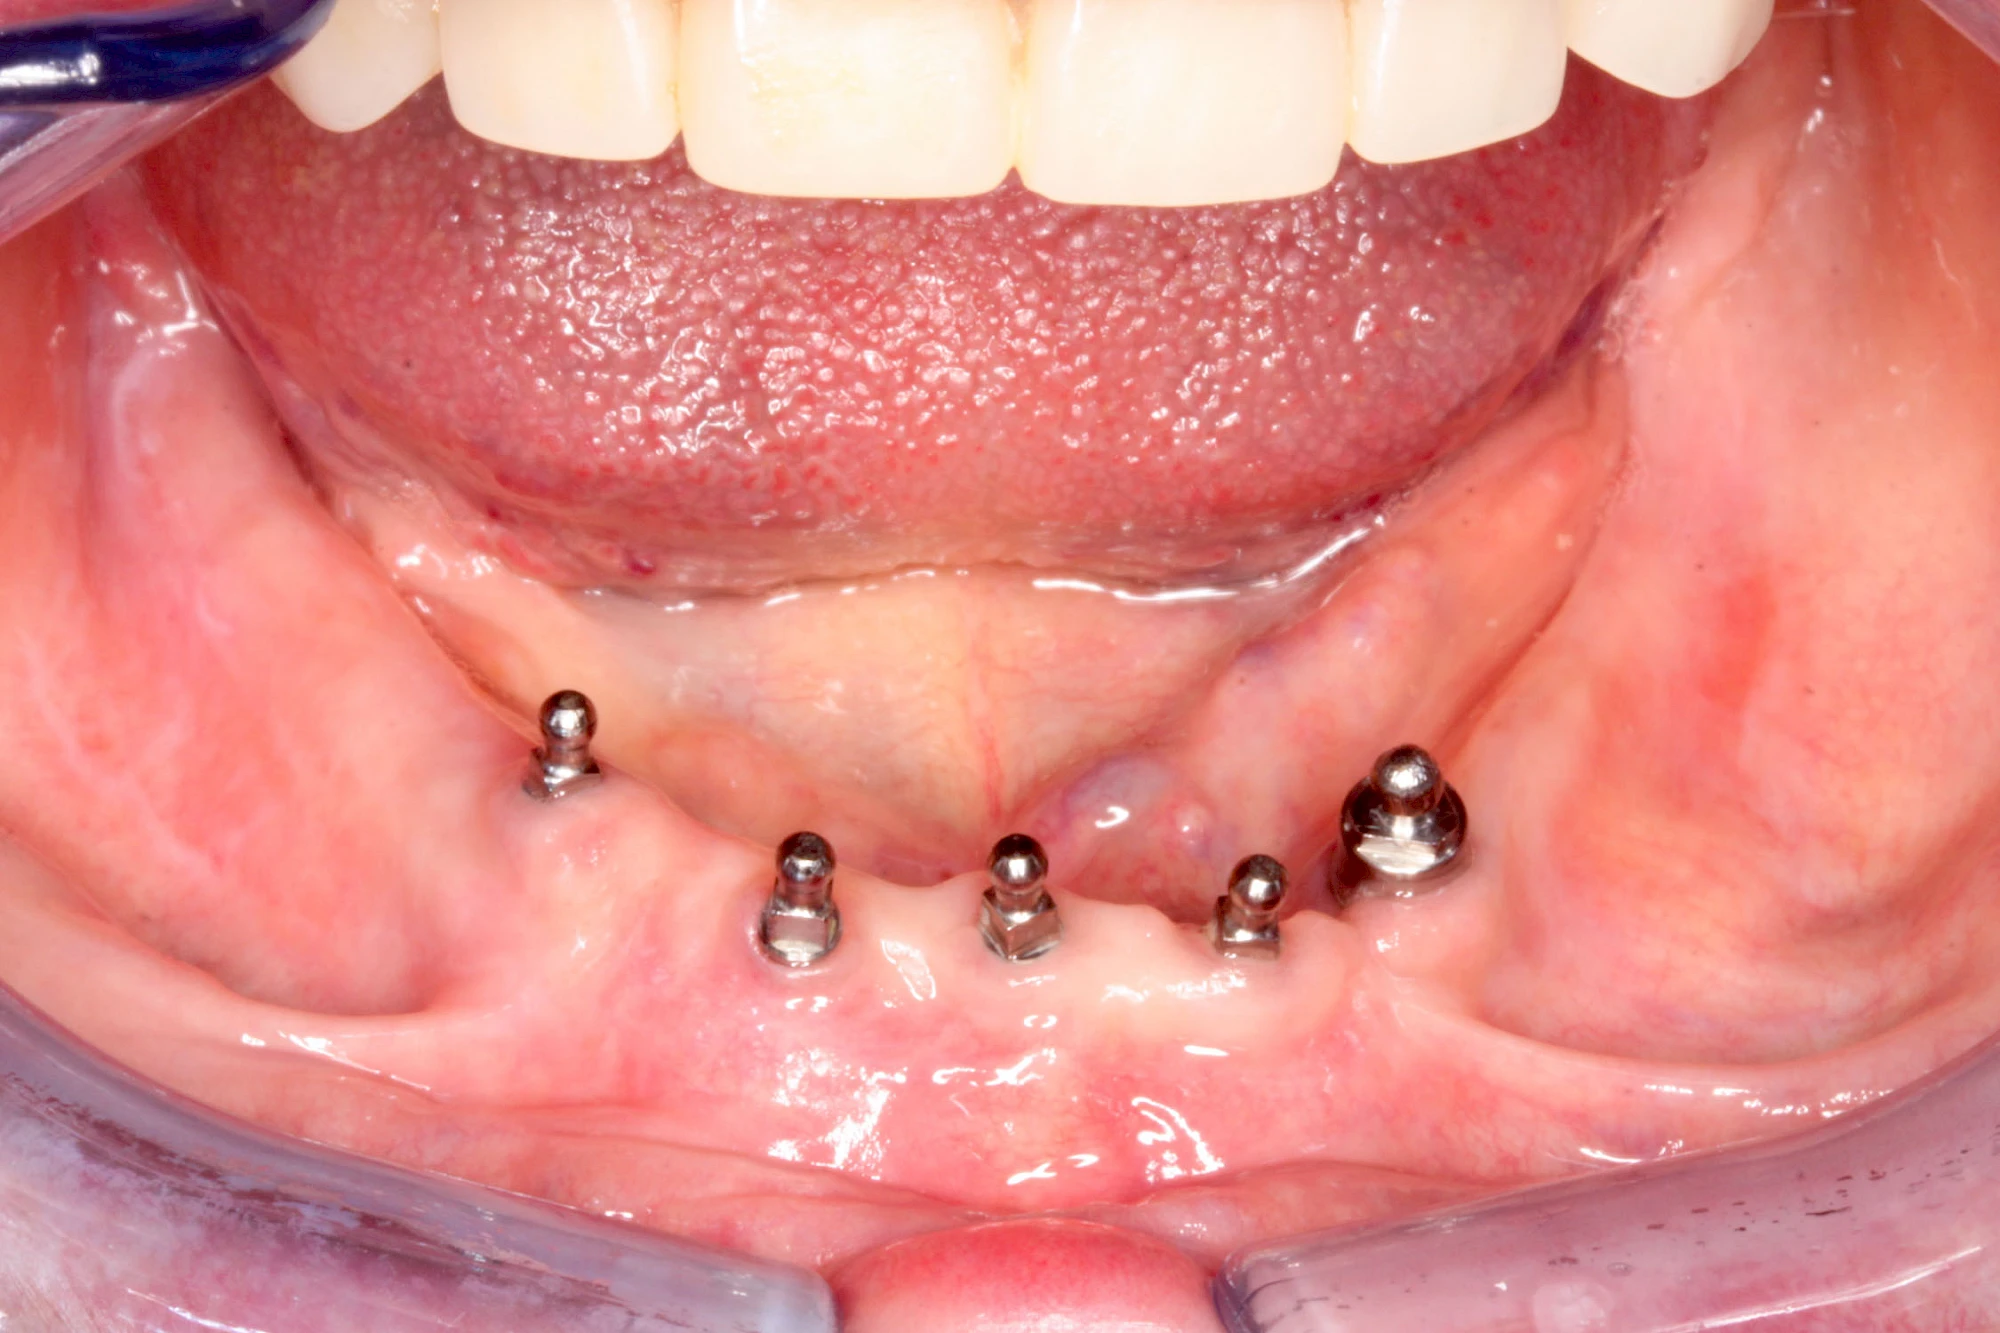

Bei herausnehmbaren Prothesen werden Implantate eingesetzt, um den Halt und den Tragekomfort der Prothesen zu verbessern. Dazu kommen verschiedene Verbindungselemente zum Einsatz:

- Teleskope

- Kugelköpfe

- Tellerförmige Lokatoren

- Stege

- Magnete (selten)

Neben rein implantat-getragenen zahnärztlichen Versorgungen werden bei herausnehmbaren Prothesen Implantate auch in Sinne einer "strategischen Pfeilervermehrung" ergänzend zu eigenen Zähnen zur Verankerung eines Zahnersatzes genutzt.

Varianten zur Verankerung von abnehmbarem Zahnersatz auf Implantaten